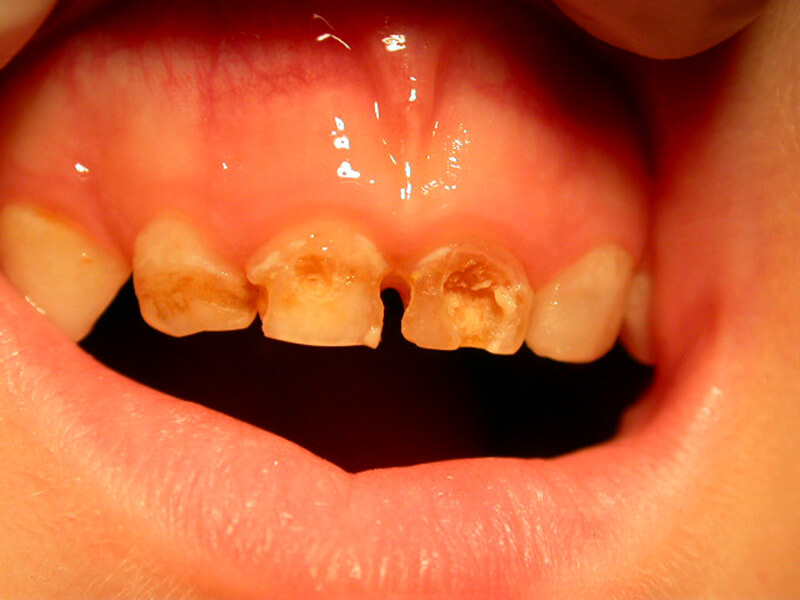

Caries is a disease. It is the most widespread disease in the world. The bacterial dental plaque (also called a biofilm) is the main cause of the infection of the teeth and the supportive tissues, i.e. of the caries and periodontal diseases respectively. The accumulation of dental plaque and the colonization of bacteria lead to the appearance of dental and periodontal pathology.

Microbes cling on various surfaces and form the biofilm. In addition, frequent intake of carbohydrates (especially sweets) gets metabolized to acids. The pH of dental plaque becomes acidic repeatedly, and that favors acid tolerant bacteria, such as streptococci and lactobacilli that are the most dangerous bacteria for caries.

Research shows that caries as a disease is identified at certain groups of people that are more prone to it. 80% of the carious cavities are located on 20% of the world’s population.